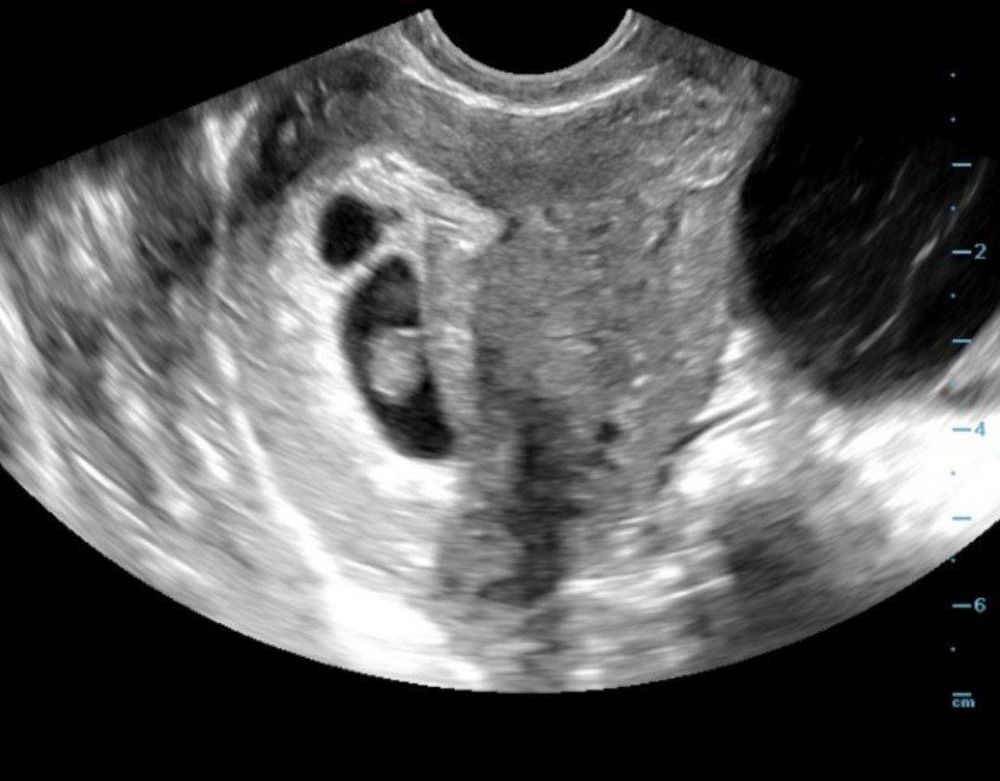

2 плодных яйца, одно пустое

На 8+1 нашли одно пя с эмбрионом сб+, второе пустое и маленькое. У кого было подобное - пустое просто рассосались, по итогу? К какому сроку? И не мог ли доктор ошибиться, и принять гематому за второе пя? Фото приложила